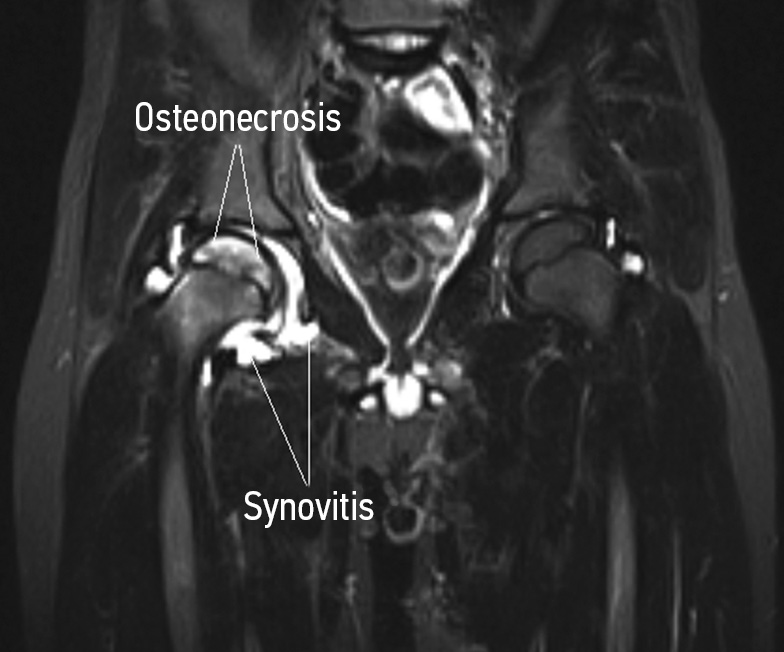

Currently, very ambiguous ideas have been formed about osteoarthritis in pediatric patients in the structure of ANFH. The mechanisms of the formation of chronic inflammation against avascular necrosis have yet to be thoroughly established. There are several theories, among which uncontrolled hyperactivity of osteoclasts, the syndrome of an exaggerated inflammatory response with overexpression of the main proinflammatory cytokines (interleukin-6 and tumor necrosis factor alpha), or the model of antiphospholipid syndrome are most consistent with ideas about the course of chronic inflammation [22, 23]. In the early stages of the disease, pediatric patients with ANFH have increased levels of the main proinflammatory cytokines in the synovial environment [24]. The role of osteoclast hyperactivity in the formation of osteonecrosis lesion has been well-established over many years of research (Fig. 1). Recent studies using immunochromatographic analysis have demonstrated overexpression of the receptor activator of nuclear transcription factor NF-κB (RANK) in the site of aseptic necrosis of bone tissue in the early stages of the disease [25]. RANK is a type I transmembrane protein belonging to the tumor necrosis factor receptor superfamily (TNFRSF). Its ligand, the type II transmembrane protein RANKL, is expressed on the surface of activated T cells, bone marrow stromal cells, and osteoblasts [26]. When the RANK receptor binds to its ligand RANKL on the cell surface, osteoclastogenesis from progenitor cells is triggered or mature osteoclasts are activated (Fig. 2) [27]. A natural antagonist of RANKL, osteoprotegerin (OPG), a so-called “decoy receptor,” functioning as a soluble homologue of RANK that blocks its interaction with RANKL. Overexpression of the OPG protein was found in the late stages of avascular necrosis in areas of active bone sclerosis [28]. Most researchers have observed the presence of concomitant synovitis in the early stages of the disease in the presence of a focus on necrosis. In contrast, synovitis was not registered in the later stages of the disease. The findings suggest osteoarthritis secondary to avascular necrosis (LCPD) may be associated with osteoclast hyperactivity. However, the lack of widespread incidence of synovitis in pediatric patients with a focus on necrosis indicates hidden molecular genetic mechanisms involved in the implementation of chronic inflammation, one of which may be the phenomenon of an exaggerated immune response [29].

Fig. 1. Magnetic resonance imaging shows the initial stage of ANFH (from the author’s archive). A magnetic resonance imaging scan reveals osteonecrosis of the femoral head on the right, massive trabecular edema, as well as pronounced symptoms of synovitis with overstretching of the joint capsule